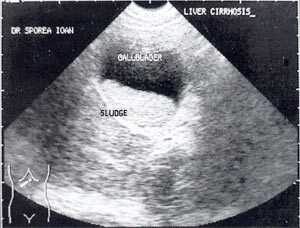

Кроме типичного вида, "желчный сладж" может иметь особый вид, похожий на круглое полипоидное объемное образование с острыми краями или неравномерным контуром ("опухолеподобный желчный сладж" или "сладжевые шарики" [12, 13]). При изменении положения больного видны перекатывающиеся или разрушающиеся шарики сладжа, затем снова формирующие исходное объемное образование (рис. 2-8).

Рис. 4. "Желчный сладж" у больного с циррозом печени.

Рис. 5. Желчный пузырь, заполненный сладжем, у больного циррозом.

Рис. 6. Желчный пузырь и "желчный сладж".